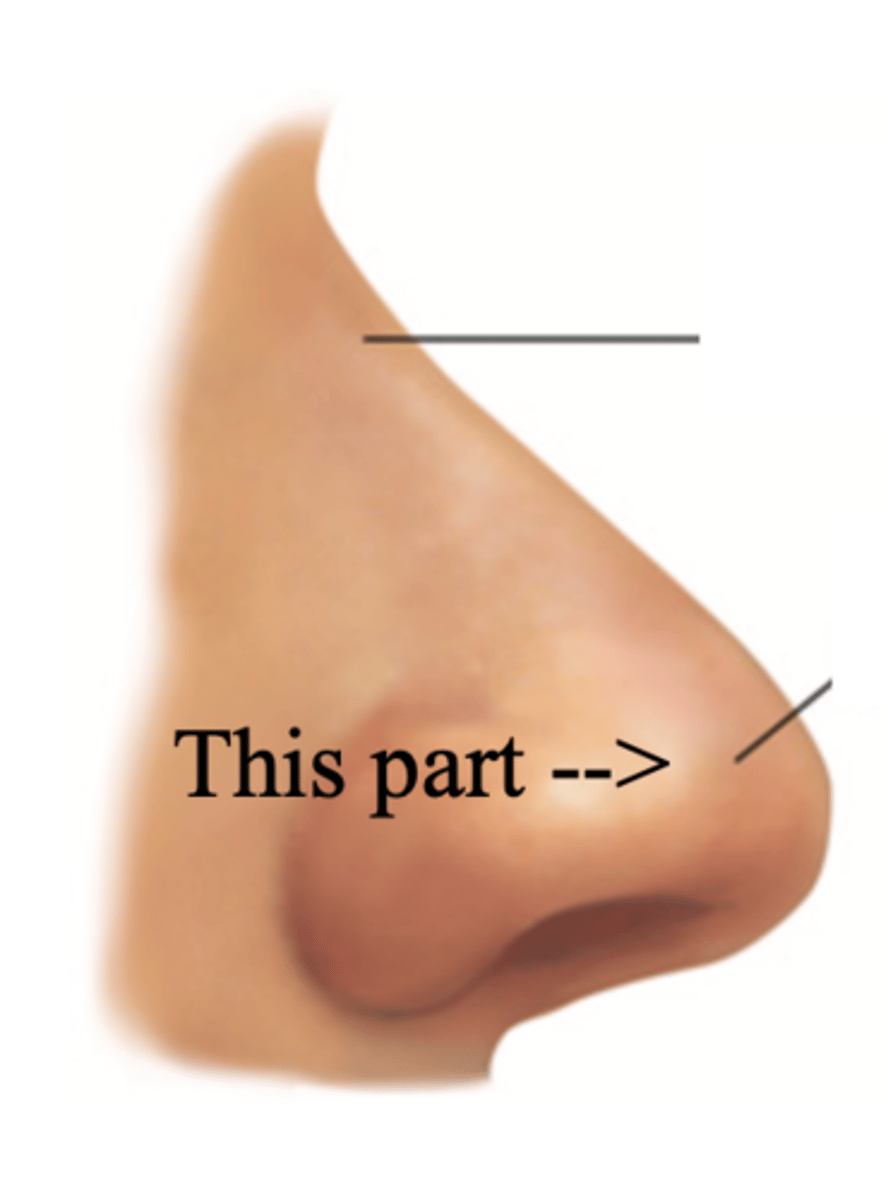

Tip